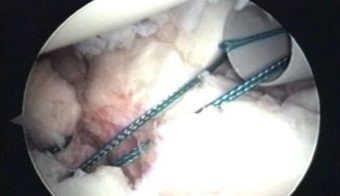

Se ha introducido un pin metálico en la zona de colocación de tornillos, los cuales serán de dos a tres en la zona de 3 a 5 ½ en hombro derecho y de 6 ½ a 9 en el hombro izquierdo según las agujas del relog